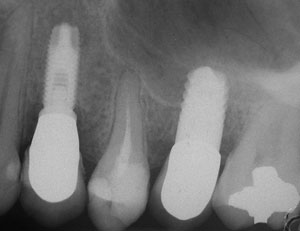

A 55-year-old male was referred for implant placement and prosthetic rehabilitation in the area of tooth No. 15. The tooth had been extracted 4 years prior. The radiograph revealed inadequate bone height for implant positioning (Figure 6). It was decided to insert an implant that was 11.5 mm in length and 3.75 mm in diameter, performing a slight osteotomic maxillary sinus lift. A heterologous bone graft also was planned to obtain a larger sinus lift.

A full-thickness mucoperiosteal flap was raised, and alternating osteotomes were used to prepare the implant site. After achieving a length of 7 mm (Figure 7A and Figure 7B), heterologous bone graft was implanted and the osteotome sequence was repeated. The implant showed primary stability.

Second-stage surgery was performed after 4 months (Figure 8); healing abutments were placed and the soft tissue was allowed to heal for 5 more weeks. Then, splinted porcelain-fused-metal (PFM) crowns supported by custom gold abutments were delivered (Figure 9 and Figure 10).

Figure 8 At 4 months after treatment, the radiograph revealed the presence of a bone layer surrounding the implant.

Figure 10 Posttreatment radiograph, after cementation of the final restorations.